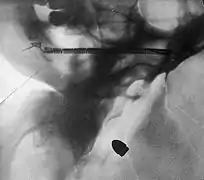

A bullet in the base of a brain, radiograph by Arthur Schuster, c. 1895

A bullet in the base of a brain, radiograph by Arthur Schuster, c. 1895 Radiograph of a pantomime artist's foot, revealing a needle by one of the toes, c. 1895